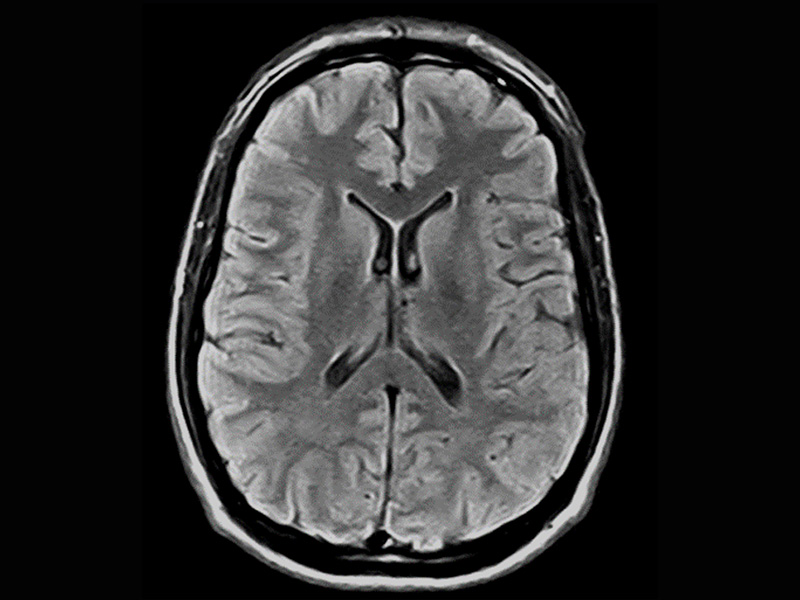

Klinické snímky